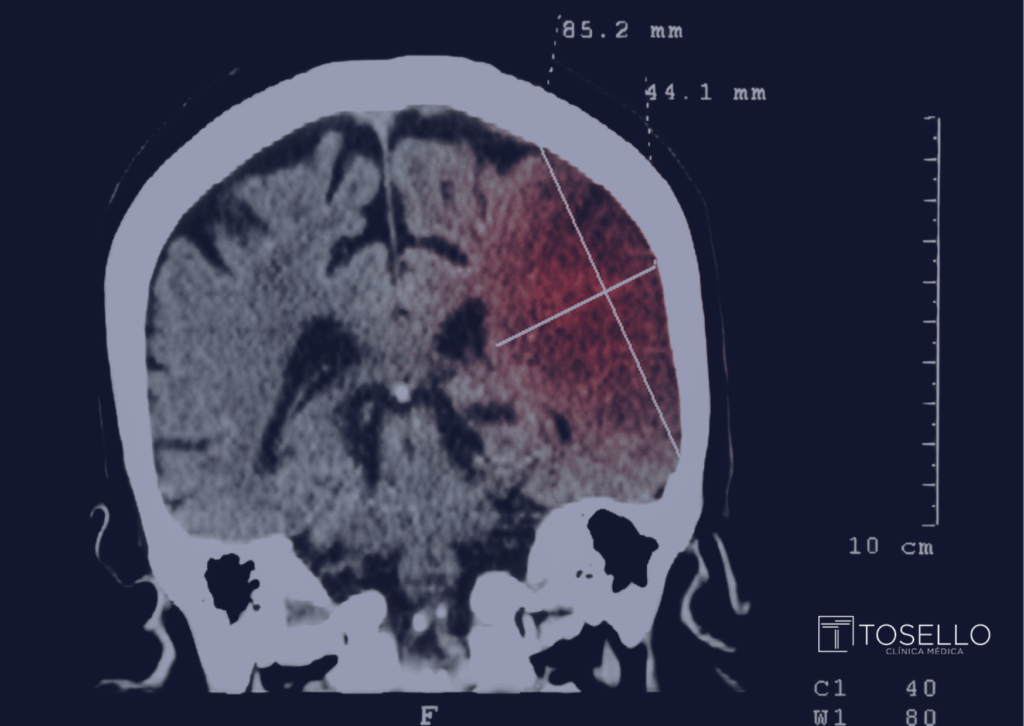

A neurorradiologia intervencionista é a área que aplica técnicas minimamente invasivas, guiadas por imagem, para diagnosticar e tratar doenças cerebrovasculares. Em vez de abrir o crânio, o médico acessa os vasos pelo punho ou pela virilha, guiando cateteres até o cérebro.

No caso do AVC isquêmico, isso significa restaurar o fluxo sanguíneo em minutos. Estudos mostram que pacientes tratados precocemente têm muito mais chances de recuperar qualidade de vida e evitar sequelas graves.